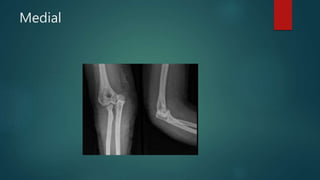

CLASSIFICATION

 Based on the direction of dislocation

 Simple versus complex

displacement of the ulna relative to the humerus

Posterior ■ Posterolateral ■ Posteromedial ■ Lateral ■ Medial ■ Anterior

Post

Medial